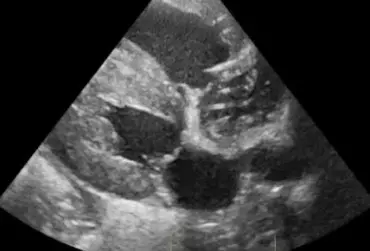

Echo serca z widoczną obecnością dużej liczby nicieni w prawym przedsionku serca (3)

16 kwietnia 2019

Wojciech Atamaniuk

Czytaj więcej